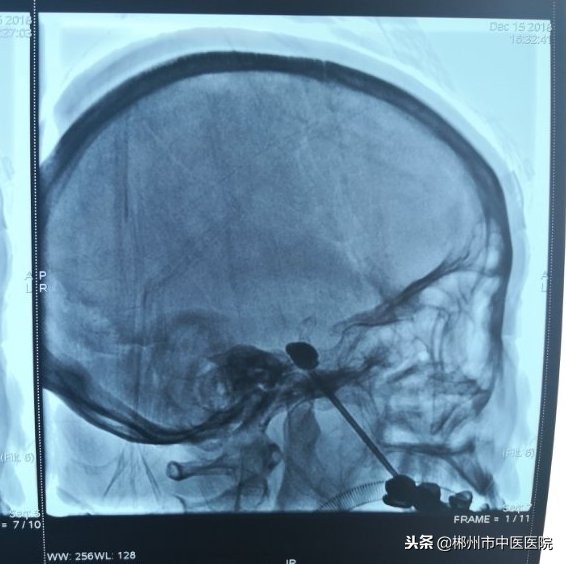

针尖抵达颅底卵圆孔,造影剂充盈球囊

手术当天,经周密术前准备,治疗开始。在麻醉科医护人员的配合下,李孝生主任从患侧口角旁经过皮肤插入穿刺针,在DSA监视下,通过鞘管将一个微球囊导入卵圆孔处三叉神经的半月节,然后缓慢注入对比造影剂充盈球囊,再通过扩张的微球囊将神经纤维压迫,从而阻断三叉神经感觉根传导功能,以达到解除三叉神经痛的效果。